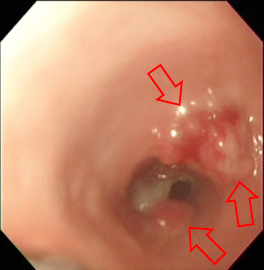

下の画像は、慢性的な嘔吐が続いていた猫の事例です。嘔吐の原因を探るために内視鏡検査を行ったところ、十二指腸の粘膜が炎症で赤く荒れていることが確認できました。

赤く見える所がひどい炎症を起こして

いるエリアで広範囲に見られています

そこで、生検鉗子で組織を採取して病理検査を行ったところ、リンパ球・形質細胞性腸炎と確定診断することができました。その後、ステロイド剤を中心とした治療プログラムを組み、嘔吐の症状は改善、消失し、治癒に持ち込むことができました。